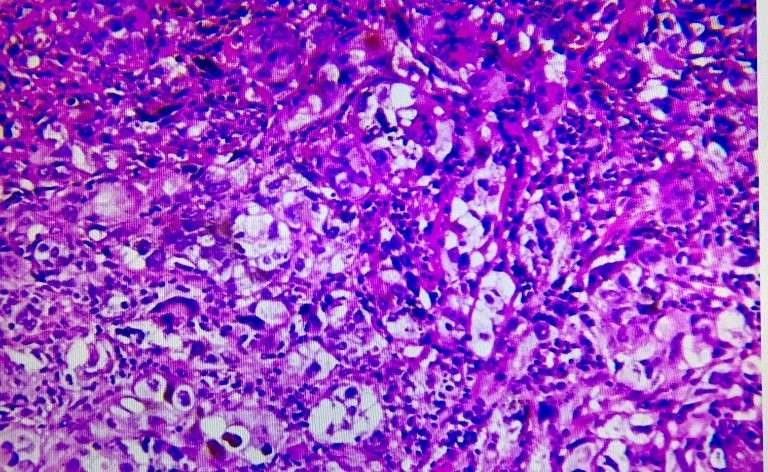

一種叫癌,這種腫瘤呢,它是上皮組織來(lái)源的。例如我們平時(shí)所說(shuō)的鱗狀細(xì)胞癌(簡(jiǎn)稱鱗癌),它是鱗狀上皮的惡性腫瘤;腺上皮的惡性腫瘤則稱為腺癌;當(dāng)然,還有二者的混合體,那叫腺鱗癌。

另一種叫肉瘤,這種腫瘤是間葉組織來(lái)源的。那么間葉組織都包含啥呢?像纖維、脂肪、肌肉、血管、淋巴管、骨和軟骨組織等這些都是的。而這些腫瘤的名稱則為:纖維肉瘤、脂肪肉瘤、骨肉瘤等。如果這個(gè)腫瘤同時(shí)具有癌和肉瘤成分,稱之為癌肉瘤。